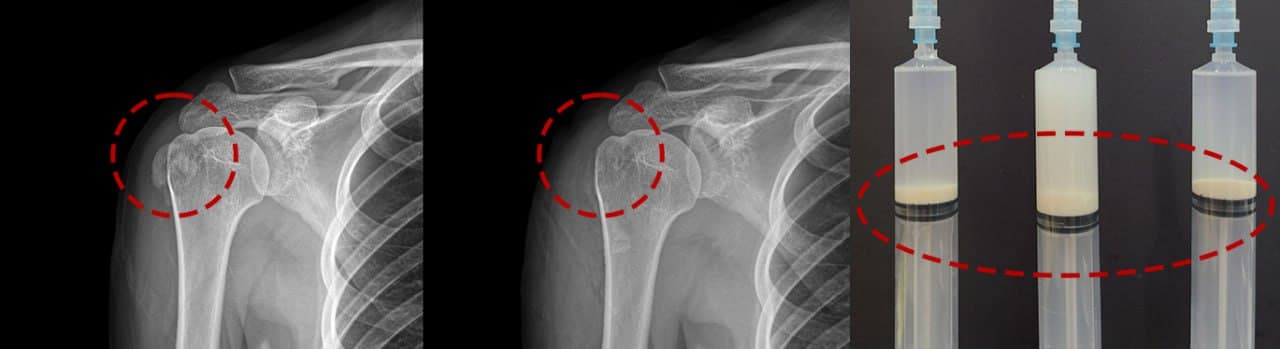

분쇄 → 흡입 → 세척 3단계

플래티넘만의 특수 분쇄 기구로 3단계를 하나의 시술로 진행합니다.

STEP 1 — 분쇄

특수 분쇄 기구가 석회에 진입하여 물리적으로 갈아냅니다. 아무리 단단한 석회도 이 단계에서 파쇄됩니다.

STEP 2 — 흡입

분쇄된 석회 조각을 강력한 흡입으로 완전히 제거합니다. 잔여물이 남지 않도록 확인합니다.

STEP 3 — 세척

마지막으로 생리식염수로 세척하여 미세 잔류물까지 제거하고 시술을 마무리합니다.